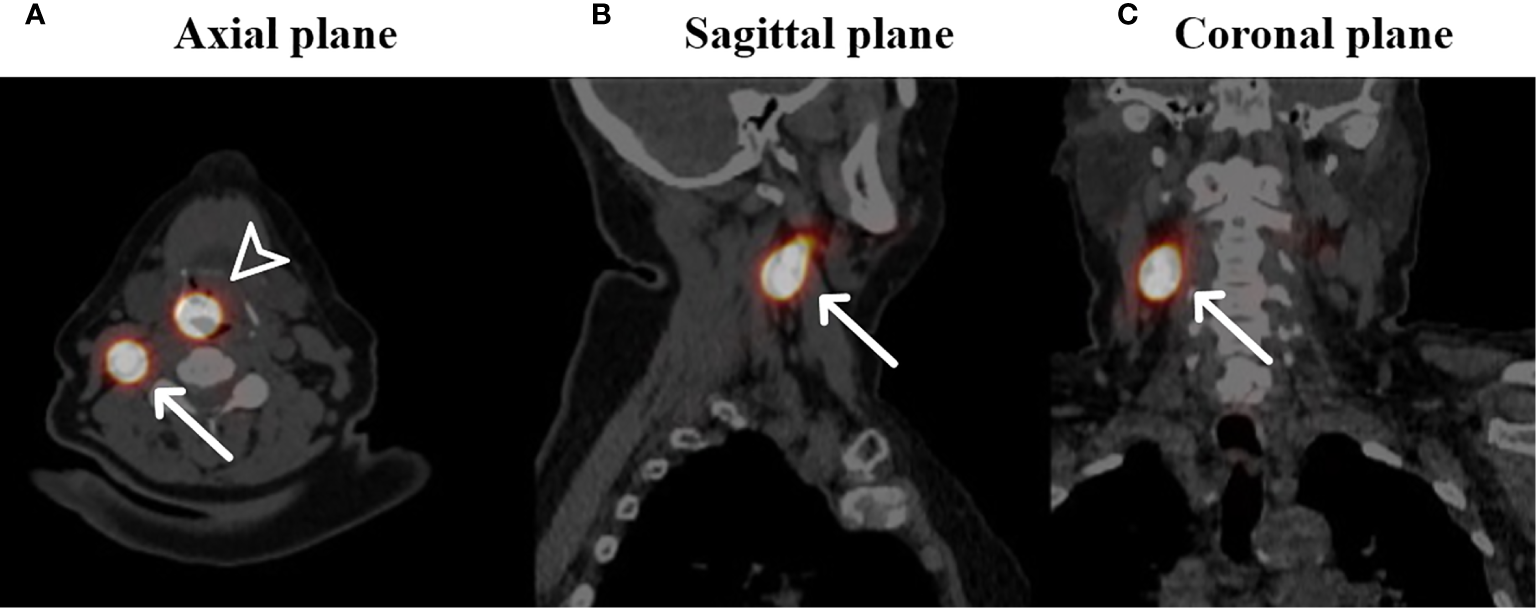

Figure 2

Fused SPECT-CT images of a patient with a cT1N0 squamous cell carcinoma located on the laryngeal side of the epiglottis who underwent SN identification (own unpublished data). Arrowhead: primary injection site of 99mTc radioisotope, white arrows: identified SN in level II on the right side in the axial plane (A), sagittal plane (B) and coronal plane (C).